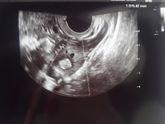

Я не много не в себе… а точнее я в приятном шоке)

Кто помнит 28 мая у меня была вторая лапароскопия+гистероскопия: удалили левую трубу, кисту, миому, прижгли эндометриоз. Расписали огромное лечение на 3 месяца. Принимала капли гинекохель+траумель, проставила … Читать далее